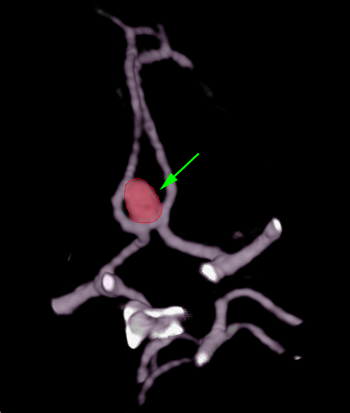

Μαγνητική, αξονική ή, κυρίως, ψηφιακή αγγειογραφία εγκεφάλου.

Η θεραπεία των ανευρυσμάτων είναι κατά κανόνα παρεμβατική με χειρουργική επέμβαση ή εμβολισμό. Η χειρουργική επέμβαση αποσκοπεί στην απομόνωση του ανευρύσματος από την υπόλοιπη αρτηριακή κυκλοφορία η οποία πραγματοποιείται με τοποθέτηση ειδικού clip στη βάση του. Ο εμβολισμός γίνεται με ενδαγγειακό καθετήρα με την βοήθεια του οποίου τοποθετούνται μεταλλικά ελάσματα εντός του ανευρύσματος με αποτέλεσμα την θρόμβωσή του.

Aneurysm1

Ανεύρυσμα (περίγραμμα)